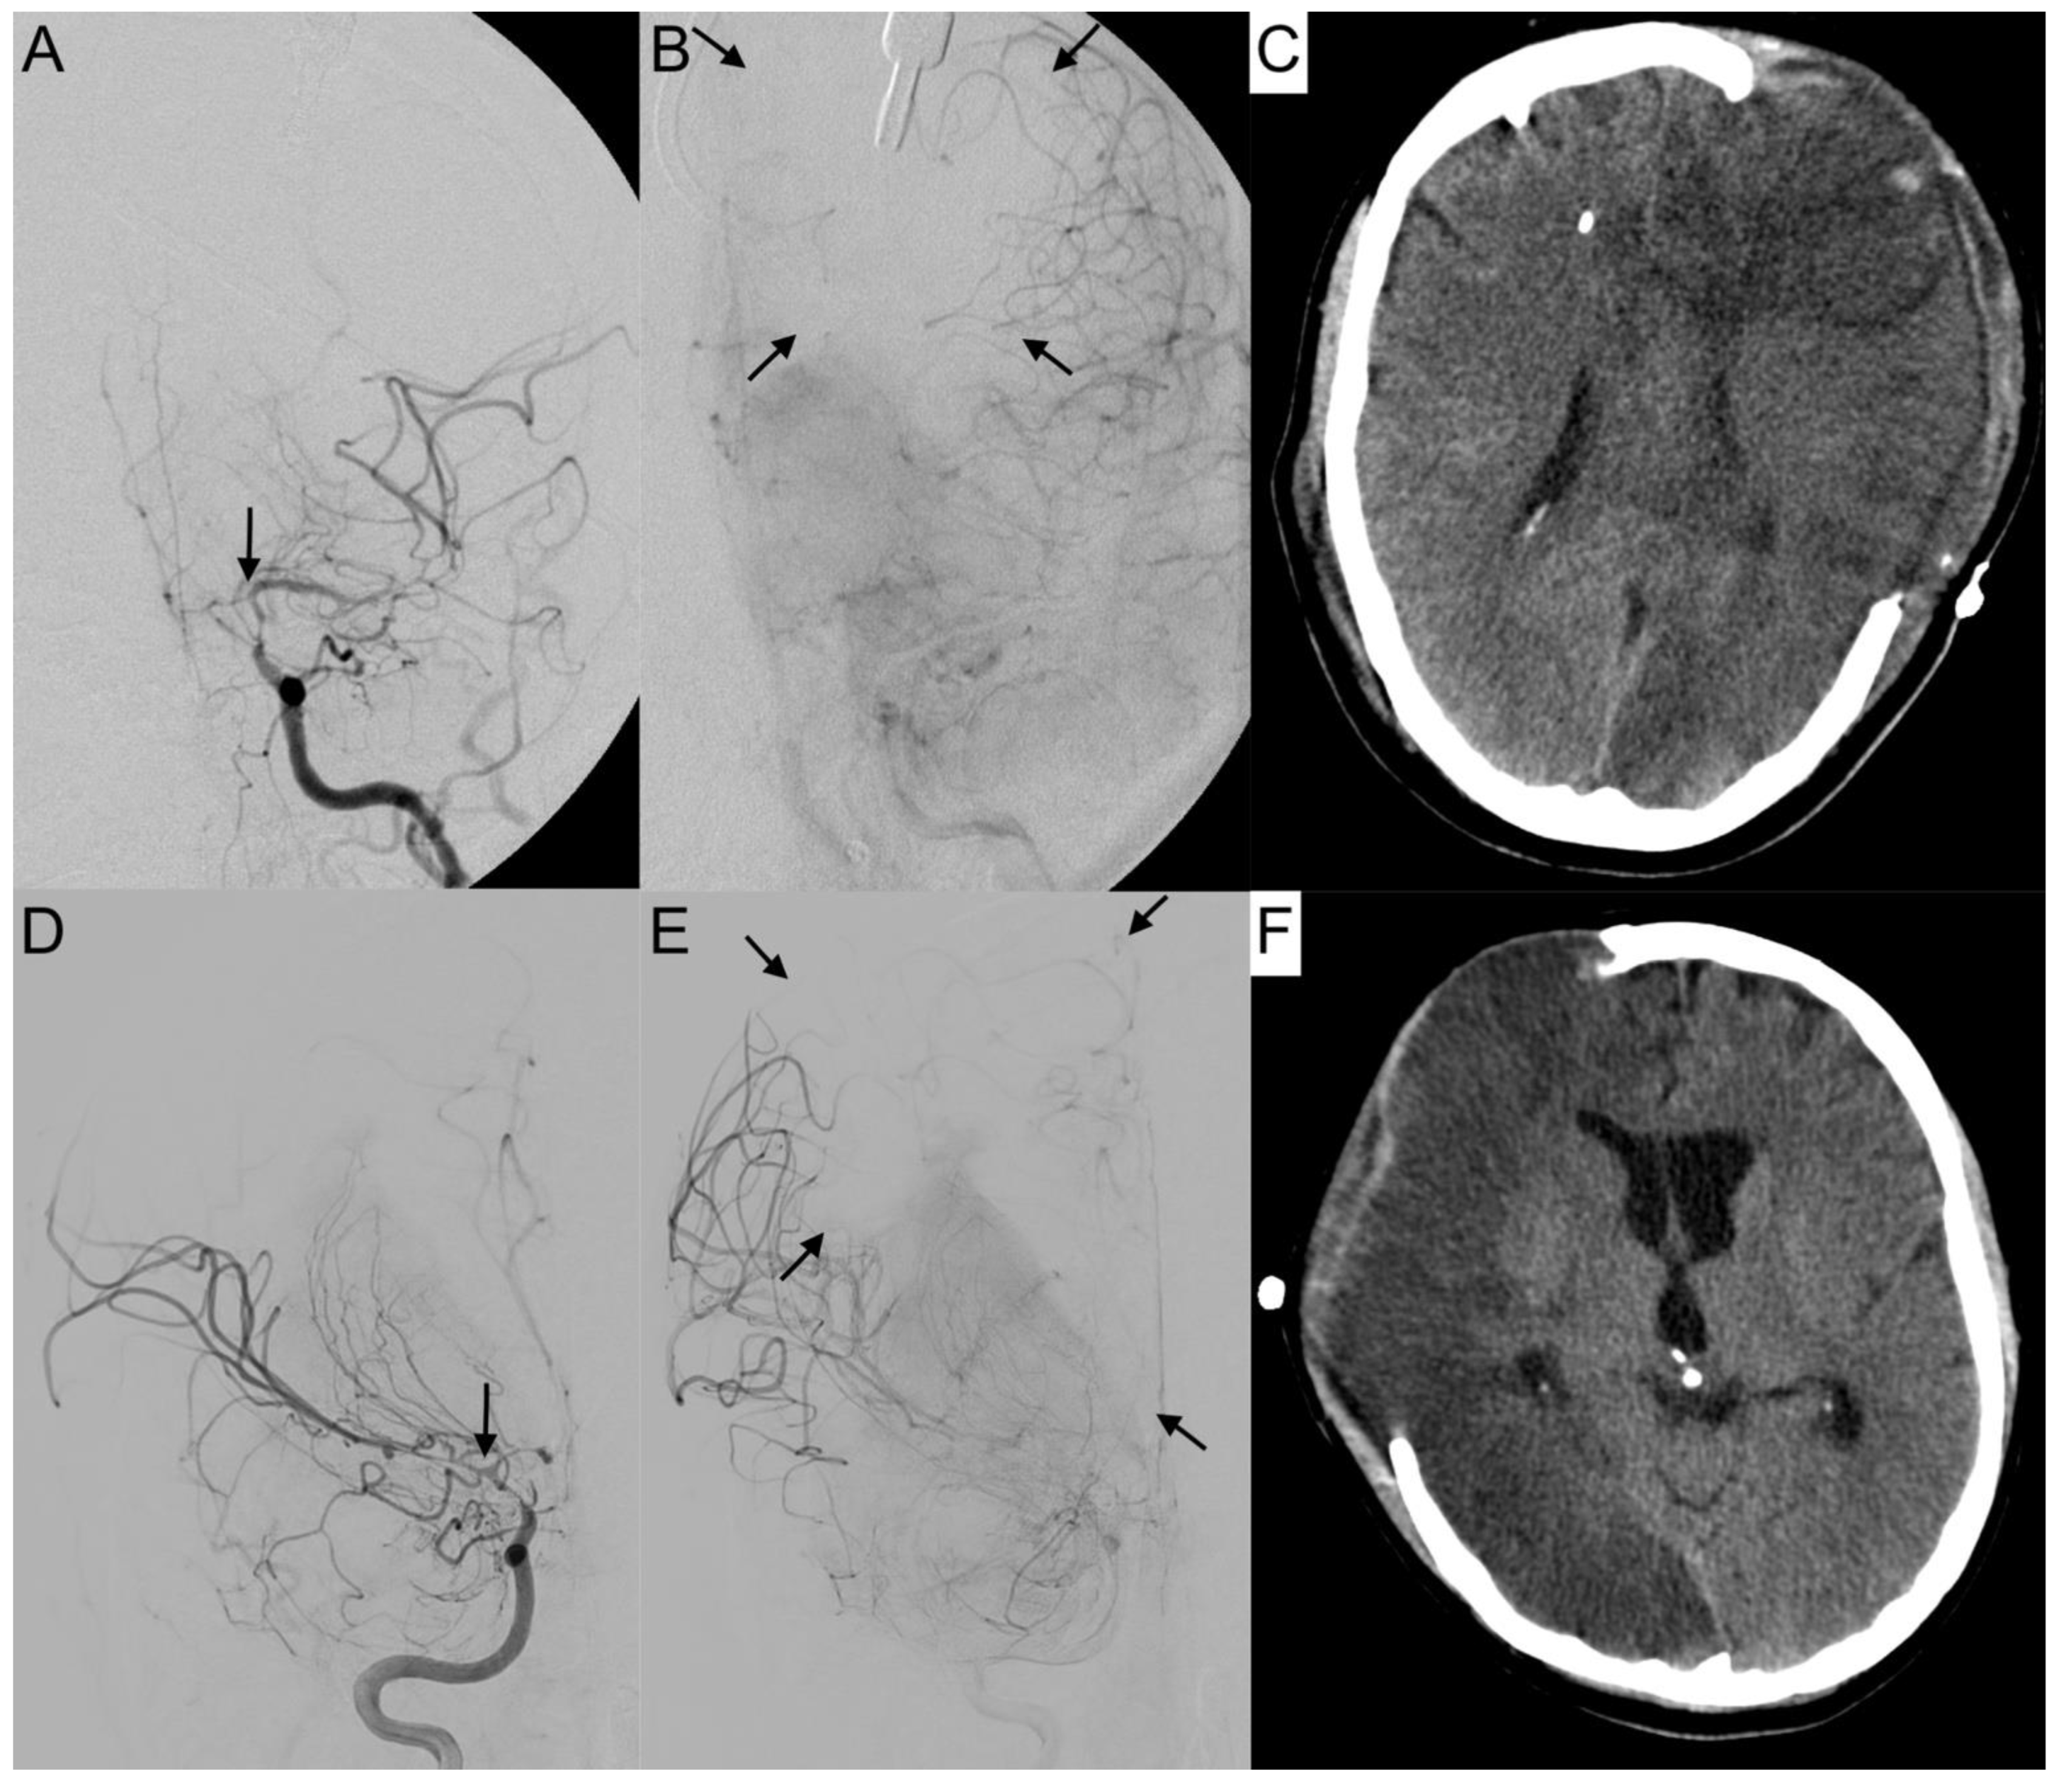

The activation of leptomeningeal collaterals between the MCA and ACA territory was assessed in p.a. projection. The varying ability of collateral supply is shown in Figure 5 and Figure 6. Two patients first had activated collateral supply, but later had collapsed collateral supply (Figure 6). The distinct outcomes with mRS values of 3 and 5, despite subtotal hemispheric infarction, were caused by the laterality of language ability.

Figure 6. Collapsed collateral supply in severe vasospasm. Angiograms of the left (A,B) and right (D,E) internal carotid arteries (ICA) with severe vasospasm (grade 3) affecting the terminal portion of the ICA (A,D: arrows) are shown. In the parenchymal phase, the breakdown of collateral supply resulted in a large perfusion deficit (B,E: arrows), leading to subtotal hemispheric infarction (C,F) in computer tomography. Both patients revealed a distinct outcome with mRS 3 (AC) and mRS 5 (D,E), depending also on the laterality of language ability.